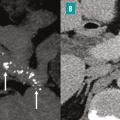

La pancréatite chronique se caractérise par des altérations morphologiques irréversibles du tissu exocrine et endocrine, associant inflammation et fibrose. C’est un continuum évoluant sur de nombreuses années. La pancréatite chronique est le fruit d’interactions multiples entre la consommation chronique d’alcool et de nicotine et des facteurs héréditaires, obstructifs, immunologiques et métaboliques. Quelle qu’en soit la cause prédominante, l’histoire naturelle et les complications restent similaires, seuls varient leur délai et leur fréquence d’apparition : insuffisance pancréatique exocrine et endocrine, douleurs chroniques, cancer du pancréas. Un bilan morphologique doit être réalisé, associant une scanographie et une pancréato-IRM. L’échoendoscopie permet le diagnostic des formes précoces et la recherche de diagnostics différentiels devant une forme focale pseudotumorale.

Le diagnostic de pancréatite chronique repose sur la réalisation d’un scanner et d’une imagerie par résonance magnétique (IRM) pancréatique afin d’éliminer les diagnostics différentiels